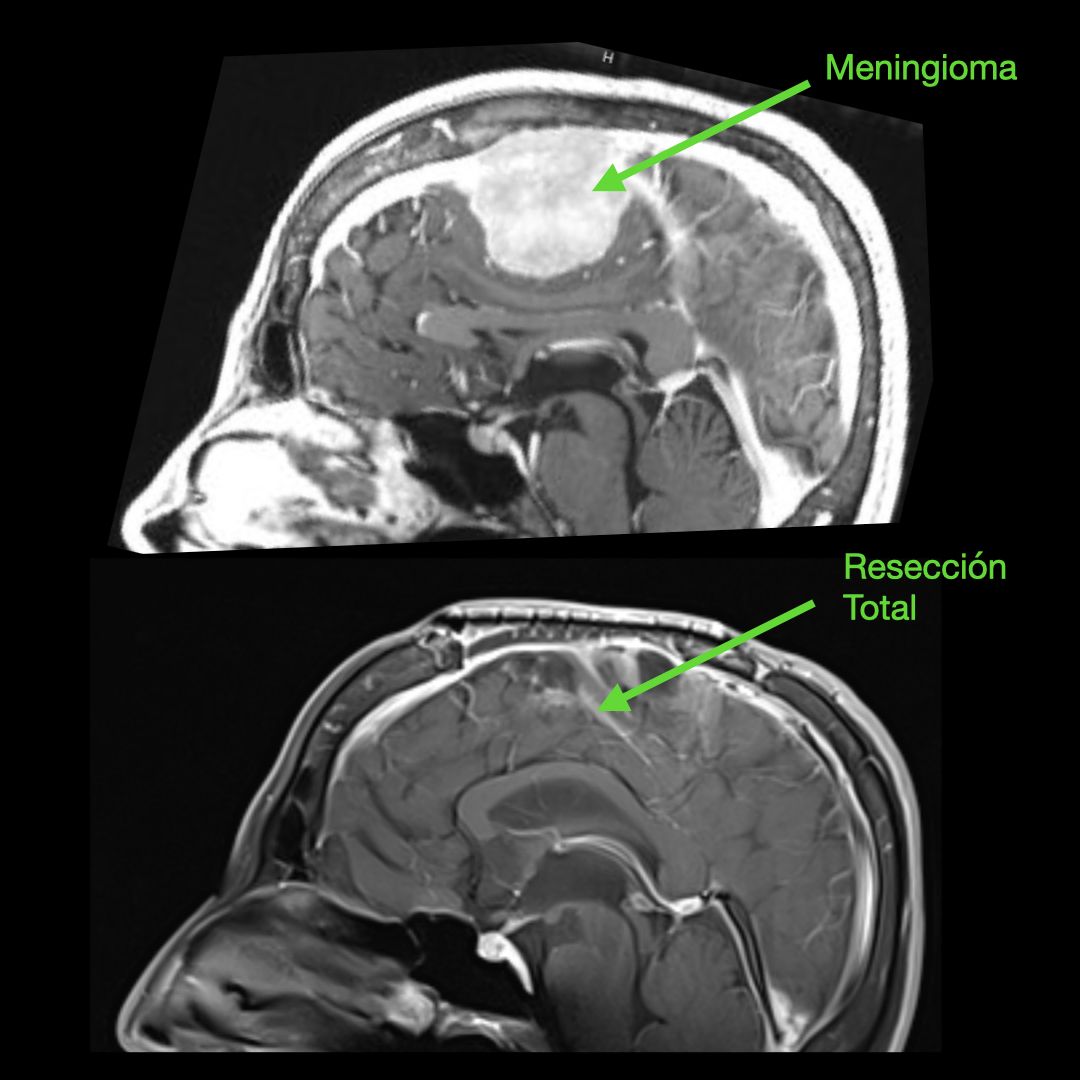

Meningiomas